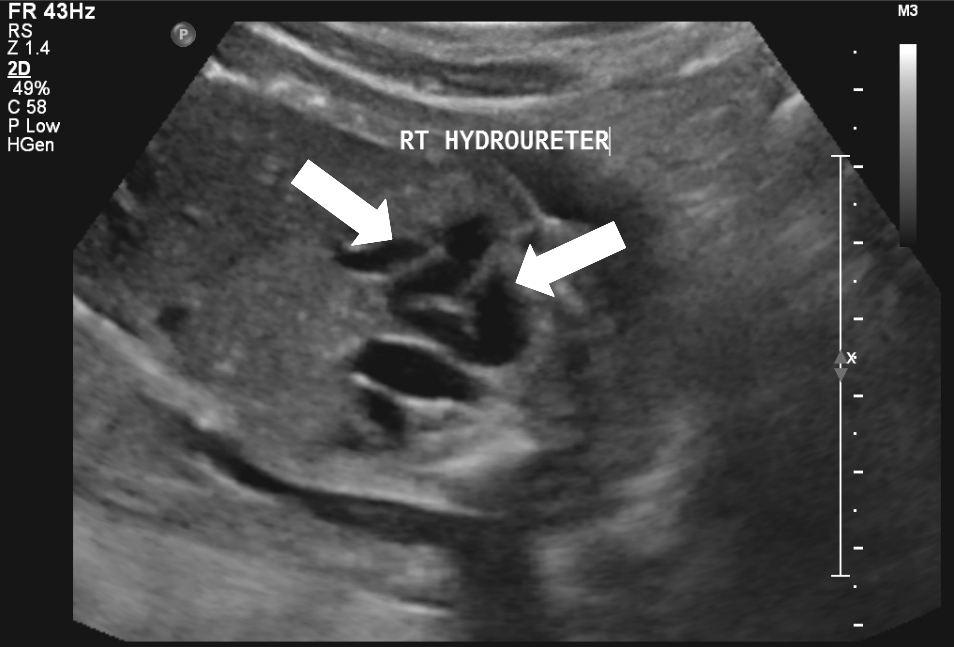

20 weken echografie: links: dikwandige blaas met verwijding van de plasbuis tot aan de kleppen (pijl): het “sleutelgat teken”. Onder: verwijde urineleiders. Bij kinderen gaan de urineleiders bij verwijding ook erg gekronkeld verlopen.

Verwijde nierbekkens (lange pijl) en nierkelkjes (korte pijl). Smalle nierschors.